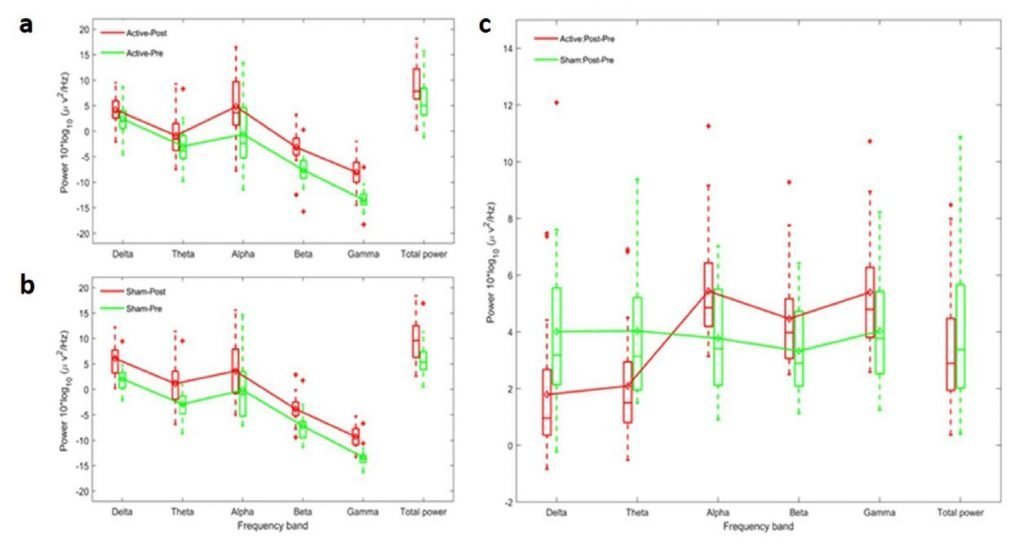

The Theory behind Pulse Rates

We have found that the pulse rate matters in brain PBM. The brain responds to pulse rate stimulation in specific ways. When we stimulate a healthy brain in gamma (40 Hz), we can elevate the amplitude of gamma and other fast waves in alpha and beta in the brain while reducing those of the slow delta and theta [3]. Independent researchers have found success in the use of the Vielight Neuro Gamma for dementia [4] , Parkinson’s Disease [5] ; and the Vielight Alpha (10 Hz) in traumatic brain injury [6] . However, please note that our devices are still general wellness device and not medical devices. We don’t claim efficacy for any indication and can only point towards research already published with our devices. (https://www.vielight.com/de//research)

- Zomorrodi, R., Loheswaran, G., Pushparaj, A., & Lim, L. (2019). Pulsed Near Infrared Transcranial and Intranasal Photobiomodulation Significantly Modulates Neural Oscillations: a pilot exploratory study. Scientific Reports, 9.